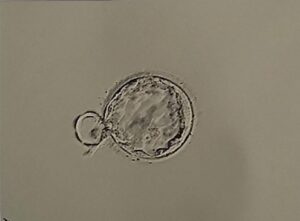

著者:アクア鍼灸治療院 「採卵したけど胚盤胞にならなかった」「胚移植がうまくいかない」──そんな不安を抱えていませんか。不妊治療の現場では、受精卵の約半数が胚盤胞に到達できないとされ、特に30代後半以降はその割合がさらに…

中でも「育卵灸」は、低温期に行うことで卵子の質の向上を目的としたお灸法で、採卵を控えている多くの方に選ばれています。